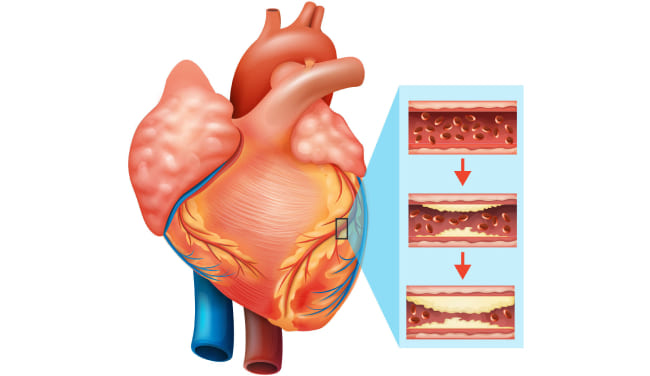

Semua orang tahu bahwa kolesterol itu buruk. Dialah yang menyumbat pembuluh darah kita, menyempitkannya, dan mengganggu sirkulasi darah. Tapi itu bukan satu-satunya penyebab, bukan?

Ya, Anda benar. Plak kolesterol atau "plak aterosklerotik" menyumbang sekitar 65-70% dari kontaminasi vaskular.

Pada usia 50 tahun, hingga 5 kg plak kolesterol terakumulasi dalam pembuluh darah seseorang. Endapan kolesterol menyempitkan lumen pembuluh darah 4-5 kali.

Bayangkan. Jika lumen normal wadah adalah jari Anda, maka 5 kg plak kolesterol mengurangi lumen menjadi ukuran 4 korek api.

Plak kolesterol sendiri tidak mengancam jiwa. Ya, kualitas hidup menurun, tekanan meningkat, ada sakit kepala dan nyeri sendi, kelemahan, dan apatis. Yang jauh lebih berbahaya adalah massa trombotik dan kristal kalsium, yang juga terakumulasi dalam pembuluh darah kita.

Penyumbatan pembuluh darah dengan kolesterol, gumpalan darah, kalsifikasi pada dasarnya adalah proses penuaan yang alami. Tentu saja, makanan modern, obat-obatan, merokok, dan alkohol mempercepat proses pencemaran ini 5-8 kali. Tapi kita semua manusia dan kita tidak bisa menghindarinya.